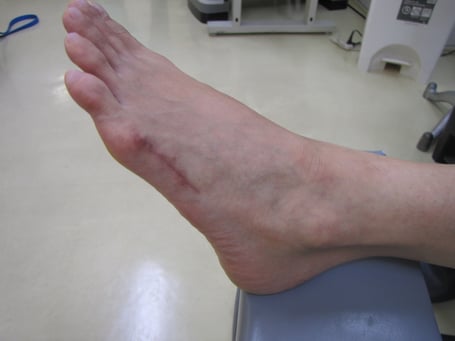

○右腓骨骨折

段差で足首をひねり下腿の二本からなる細い方の骨が折れてしまいました。受傷翌日には皮下に真っ黒な皮下出血と腫れが認められます。

一般的に整形外科では膝下から指先まで長靴のようなギプスを巻きます。ギプスの底にはヒールと言ってゴムの踵のようなものをつけます。寝る時も着けっぱなしなのでストレスがたまります。皮膚が痒くなるばかりか悪臭もしてきます。

整骨院では昔ながらの固定法で、毎日ギプスを外し浮腫を取るマッサージ、皮膚の衛生管理、超音波による骨癒合を促進させます。

ギプスを外してからリハビリでなく、受傷日からリハビリにより回復をはやめます。